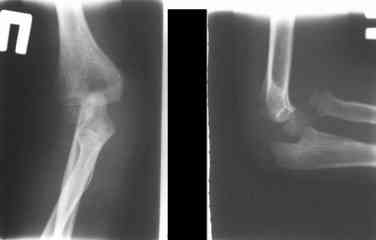

Иллюстрация к лечению застарелого повреждения Монтеджиа

Пациентка клиники детской травматологии ЦИТО

На рентненграмме видна деформация локтевой кости на границе верхней и средней трети. Ведь там был перелом.

Уважаемые коллеги, кто-нибудь еще видит здесь застарелое повреждение Монтеджи? Может мне показалось?

Колеги!!! Сконцентрируйтесь... Не спешите и подумайте, что препятствует головке луча вернуться на свое место??? Отвыкание :):):) Конечно нет. Внимательно посмотрите на ось локтевой кости. Как раз она мешает вернуться лучу на место. Зря Монтеджи старался, что ли???

Многоуважаемые коллеги, всем большое спасибо!!! Да, здесь было повреждение Монтеджиа, когда нарисовал скиаграмму все стало понятно. Мне очень понравились рекомендации Константина Требухина, только немножко видоизменил; я считал так, если деформацию исправить то локт/кость должна удлиниться, и во вторых, если на аппарате низвести лучевую кость, то может наступить позиционное несоответствие в дистальном радиоульнарном сочленении. 28.02.08г операция - шарнирная остеотомия локтевой кости на уровне деформации, далее вскрыт плечелучевой сустав, удалены рубцовые тканы, после исправления варусной деформации и создания физиологического изгиба локтевой кости головка луча легко вправился, из части рубцовой ткани сделана пластика кольцевндной связки, трансартикулярная фиксация спицей, локтевая кость двумя спицами.